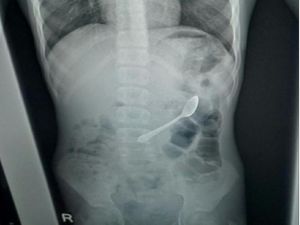

Ngilu! Bocah Ini Tak Sengaja Telan Sendok, Baru Dikeluarkan 10 Hari Kemudian

Dokter menemukan sebuah sendok sepanjang 11 cm di dalam tubuh bocah berusia 13 tahun. Sendok itu baru dikeluarkan 10 hari setelah tertelan.